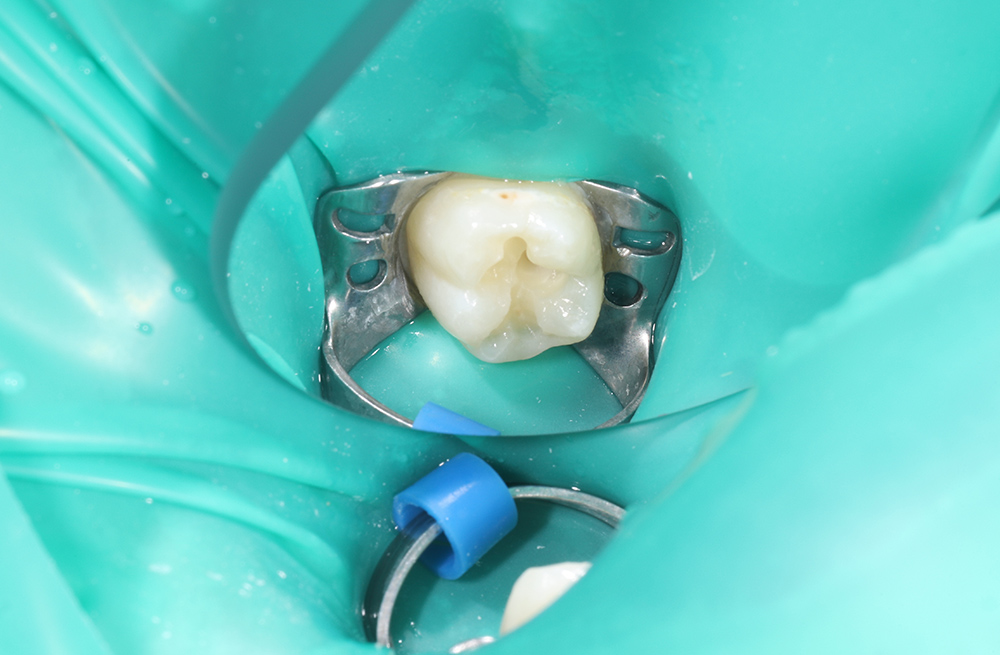

Лечение кариеса на жевательной поверхности постоянного зуба у подростка